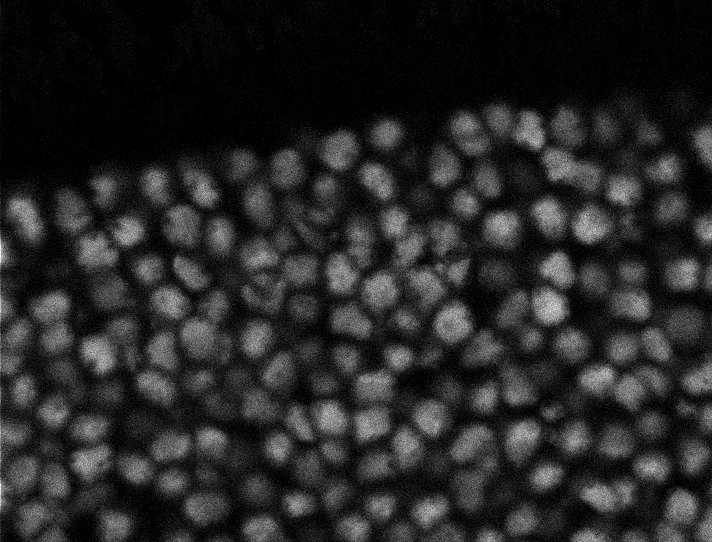

Nuclei